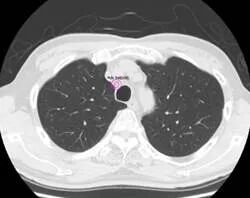

分析CT图像以检测肺部结节(疑似肺癌);

其中关于分析CT图像以检测肺部结节(疑似肺癌)的功能,我们的检测性能是现有研究中最高的,其灵敏度达到了98.3%。

我们核心技术是一种显示结节的人工智能,通过在CT扫描获得的图像中的CT值显示最大直径为3厘米或更小的圆形、纺锤形或不规则边缘的吸收增加的ROI区域,提高结节阴影和其他ROI区域的可见度。